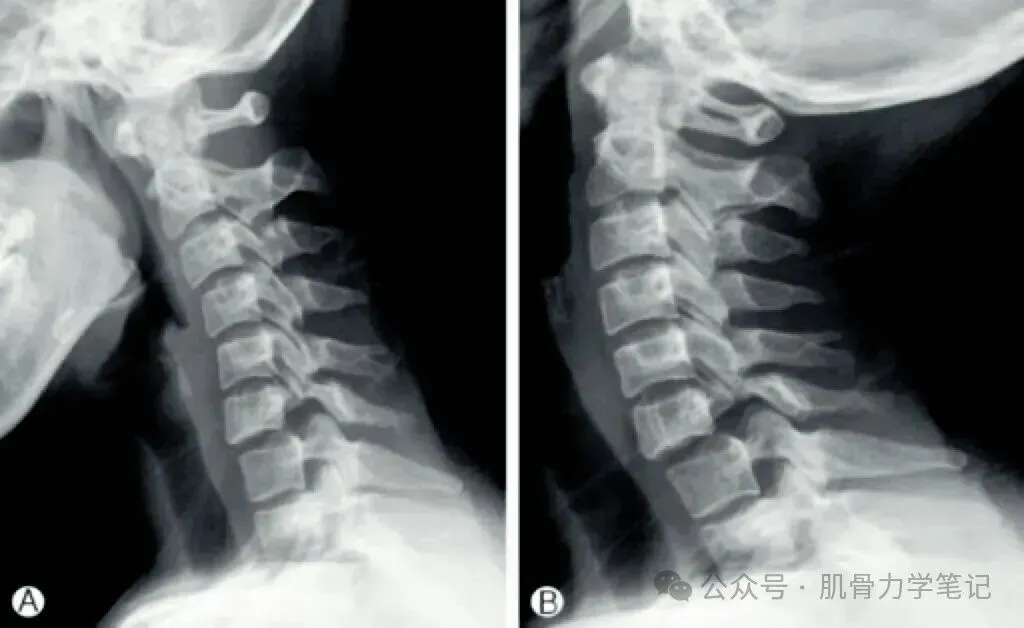

4. 过屈/过伸位(动力位):用于评估脊柱稳定性

颈椎动力位片示C6滑脱